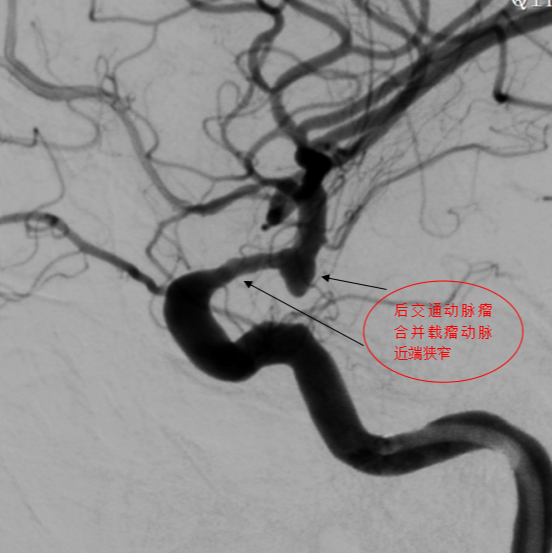

第三例患者确诊为后交通动脉瘤伴近端血管狭窄,双重病变增加了手术难度。团队选择合适尺寸血流导向装置,支架完美打开,即刻动脉瘤内出现造影剂滞留,患者术后2天出院。